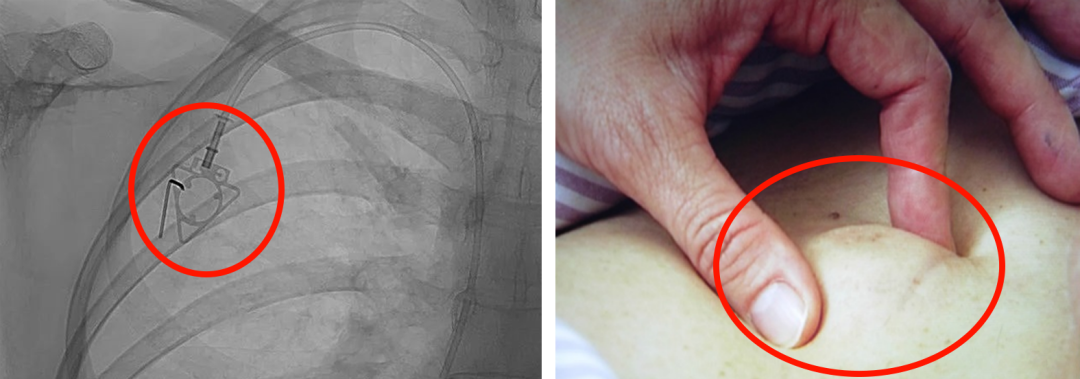

輸液港,臨床上也稱為PORT,是為了減輕藥物對(duì)患者血管刺激而置入體內(nèi)的專業(yè)輸液裝置。它分為三部分:無損傷針、置入靜脈的導(dǎo)管、埋藏在皮下與輸液針連接的注射座(港體)。注射座連接插入大靜脈的導(dǎo)管形成長期血管通路,發(fā)揮類似港口的作用,故稱作“輸液港”。

微信圖片_20220425080014.jpg

微信圖片_20220425080333.png